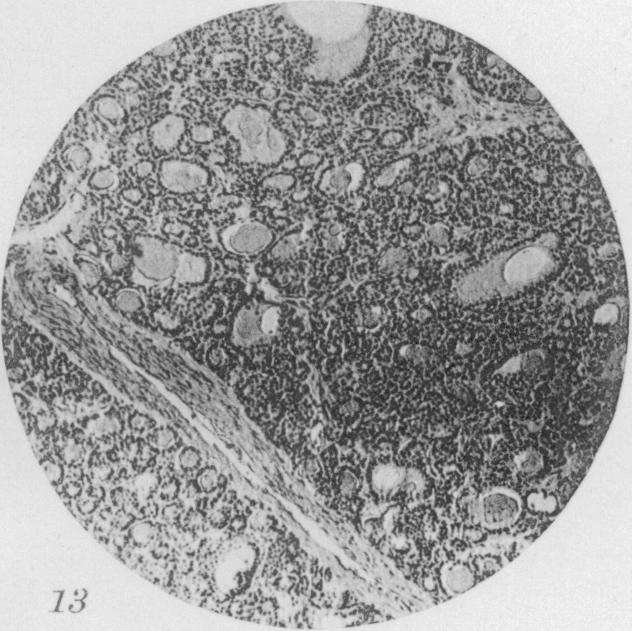

Benign Epithelial tumors of the Thyroid Gland.

J Med Res. 1913 Jan;27(3):229-268.5.